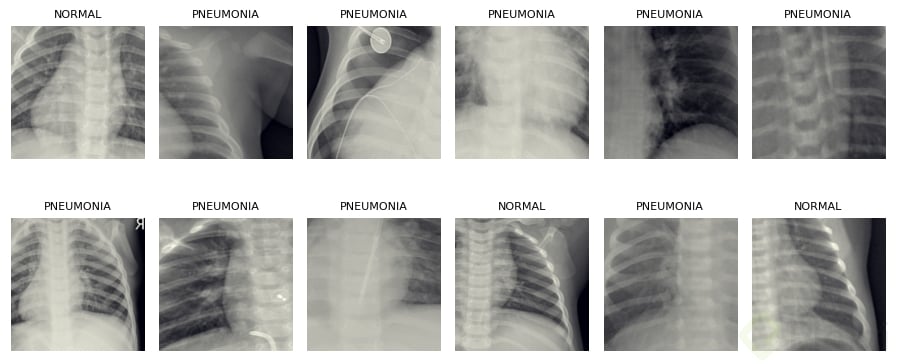

Pueden verse las clases y dimensiones del dataset para asegurar que todo cargó correctamente.